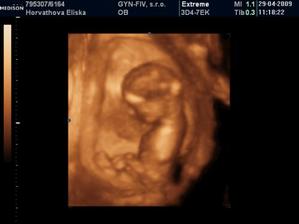

Dvojicky po KET

tak sme sa dockali-nase dvojicky sa narodili v 37+1 tt -20.10.09 cisarskym rezom -11:00 Matúško 3150g a 48cm a 11:02 Natálka 3030g 48cm,